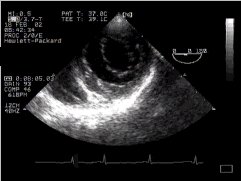

1. The LV short axis view at the level of the papillary muscles (TG Mid SAX)

2. The following pictures show (on the right) an echocardiographic image of the LV short axis, and on the left, an anatomical image taken from the visible human project. If you move your mouse over the left image, then the picture should change to a labelled one, with the right (RV) and left (LV) ventricular cavities clearly visible, the interventricular septum (ivs) between, them, and the strangely named inferior, posterior, and anterior walls of the left ventricle shown (iw, pw and aw respectively) together with their blood supply. The territory supplied by the left anterior descending coronary artery is shown in green, that supplied by the circumflex in red, and the right coronary artery territory in blue.

UP transgastric view of left ventricle CLICK FOR VIDEO: transgastric view

The papillary muscles are also labelled (pm = posteromedial, al = anterolateral). (If anything, the anatomical section is a bit too close to the mitral valve, and the papillary muscles are thus smaller in cross section - we've taken this section because in sections nearer the apex, the left ventricular cavity is minuscule). In addition, the left ventricle in the visible human is very poorly filled, so the wall appears thickened, and the cavity diminished. Note that coronary anatomy varies considerably from individual to individual, so the above supply doesn't necessarily apply to everyone. Use the information contained in an angiogram of the patient, if you have this!